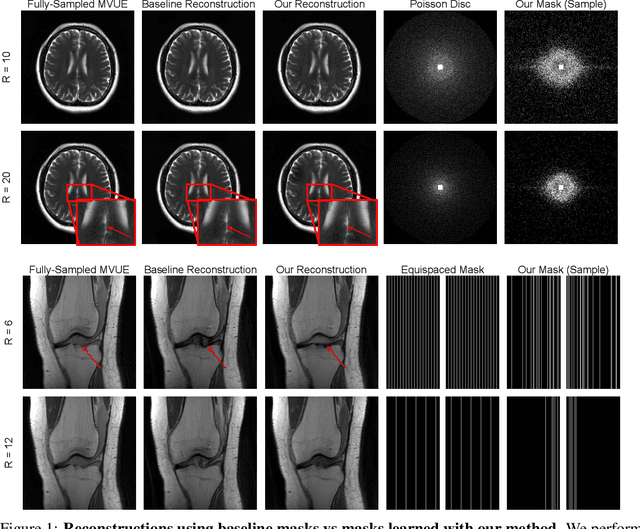

Abstract:Diffusion-based generative models have been used as powerful priors for magnetic resonance imaging (MRI) reconstruction. We present a learning method to optimize sub-sampling patterns for compressed sensing multi-coil MRI that leverages pre-trained diffusion generative models. Crucially, during training we use a single-step reconstruction based on the posterior mean estimate given by the diffusion model and the MRI measurement process. Experiments across varying anatomies, acceleration factors, and pattern types show that sampling operators learned with our method lead to competitive, and in the case of 2D patterns, improved reconstructions compared to baseline patterns. Our method requires as few as five training images to learn effective sampling patterns.